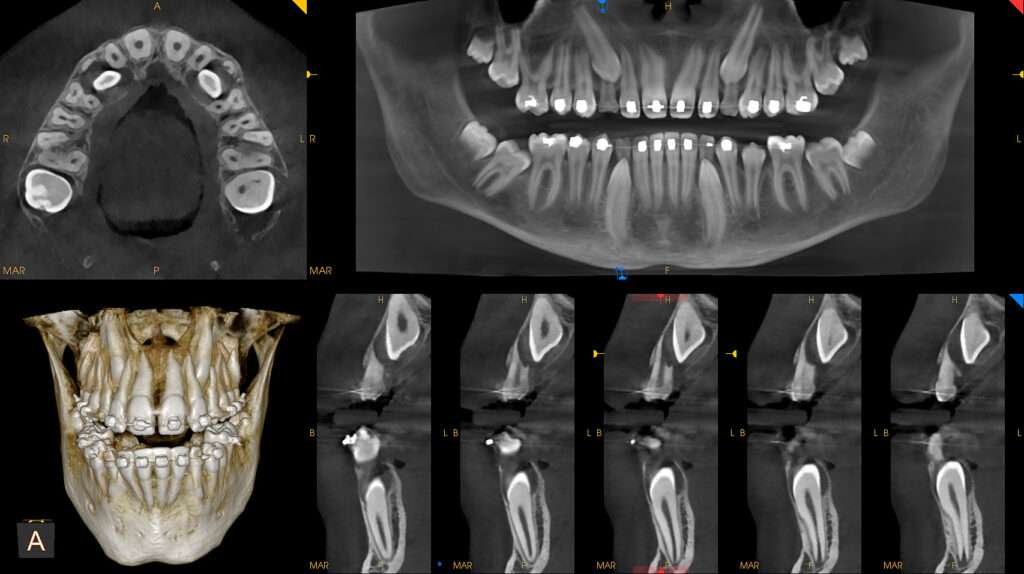

Głównym urządzeniem do dokładnej diagnostyki jest tomografia cbct z polem obrazowania od 5×5 cm do 17×13,5 cm z możliwością wykonywania zdjęć tomograficznych i pantomograficznych w jednym urządzeniu.

System 9300 CS zawiera oprogramowanie, które jest nie tylko wyposażone w różne funkcje wspierające przygotowanie planu leczenia, ale również jest doskonałym narzędziem do komunikacji z pacjentem. Aplikacja pozwala na przeglądania warstwa po warstwie przekrojów osiowych strzałkowych koronalnych skośnych i trans-wersalnych pozwalając na szybkie uzyskanie pełnej informacji niezbędnej do postawienia trafnej diagnozy. Oprogramowanie zawiera w sobie bogatą bazę implantów różnych producentów które umożliwiają dokładną diagnostykę do wykonywania zabiegów implantologicznych.